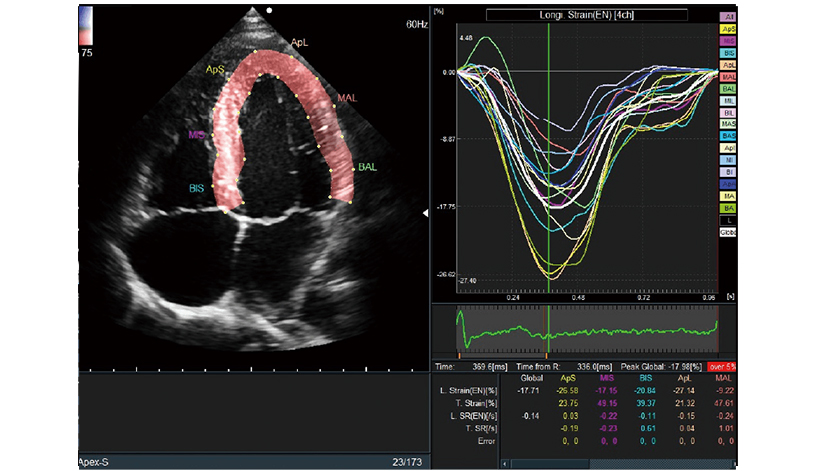

i2DTT

Yapay zeka teknolojisini kullanarak, 2 Boyutlu izleme yöntemiyle çeşitli ölçümleri tam otomatik olarak gerçekleştirir. Bunlardan biri olan Global Boylamsal Gerinim (GLS), kalp yetmezliği muayenelerinde dikkat çekmektedir.